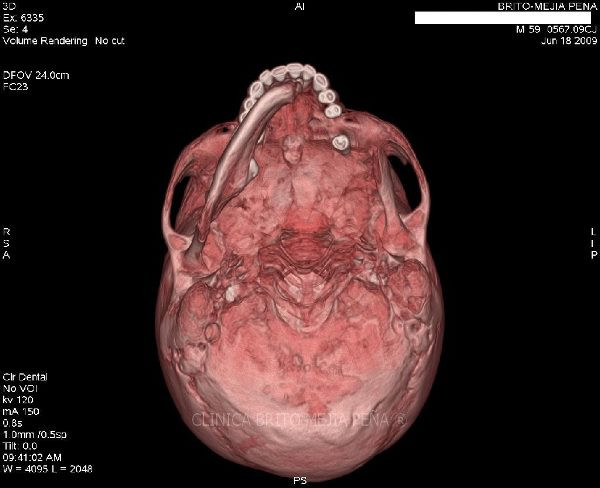

Envíado por BMP Imágenes Diagnósticas

BMP Imágenes Diagnósticas